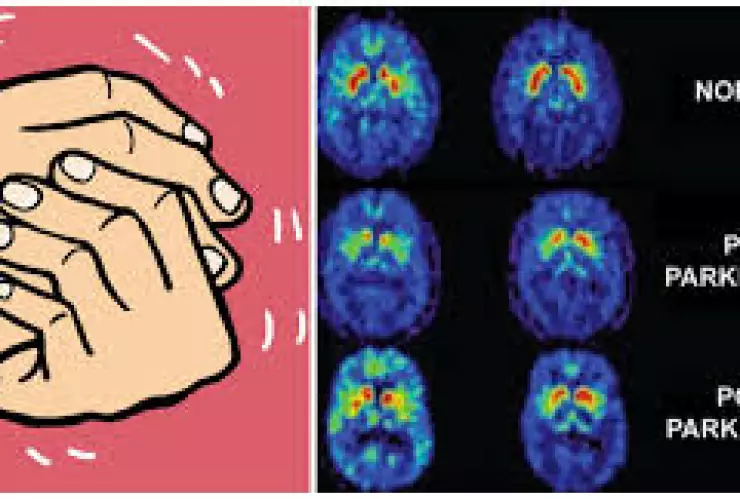

Los síntomas son motores y no motores. Los síntomas motores son aquellos que te afectan de manera física como la lentitud al realizar actividades, el temblor de manos, pies y cabeza, la estabilidad y el equilibrio, la rigidez o espasticidad, la coordinación, etc. Los síntomas no motores son aproximadamente de 50 a 60 según el Dr. Rodrigo Llorens (neurólogo) ; algunos de estos síntomas son la de presión, la apatía o ansiedad, trastornos de sueño, fatiga, confusión, etc.